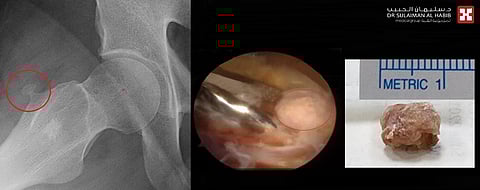

مؤكداً أنه على الفور تم إخضاع المريض للفحص السريري، وتبين وجود شد والتهاب بالرباط الحرقفي الظنبوبي، وبإجراء مجموعة من التحاليل المخبرية والفحوصات بالأشعة السينية الرقمية (Digital X-Rays) والرنين المغناطيسي (MRI)، كشفت النتائج عن وجود ورم عظمي غضروفي حميد بطول واحد ونصف سم بمنطقة ما بين المدورين في الورك، والتهاب حاد واضح بجراب المدور الأكبر وشد بالشريط الجانبي بالورك.

مشيراً إلى أن عملية المنظار بالورك استغرقت ساعة، وتم فيها عمل فتحتين صغيرتين بالجلد وصولاً للشريط الحرقفي الظنبوبي، والبدء في تطويله مع تنظيف الجزء الملتهب من المخدة الدهنية، ومن ثم ادخال المنظار بين الشريط الجانبي وعضلات الورك الأمامي وبالإستعانة بالأشعة التداخلية إذ تم الوصول إلى الورم العظمي الغضروفي وإزالته خارج المفصل مع إجراء تنظيف لكامل المكان.